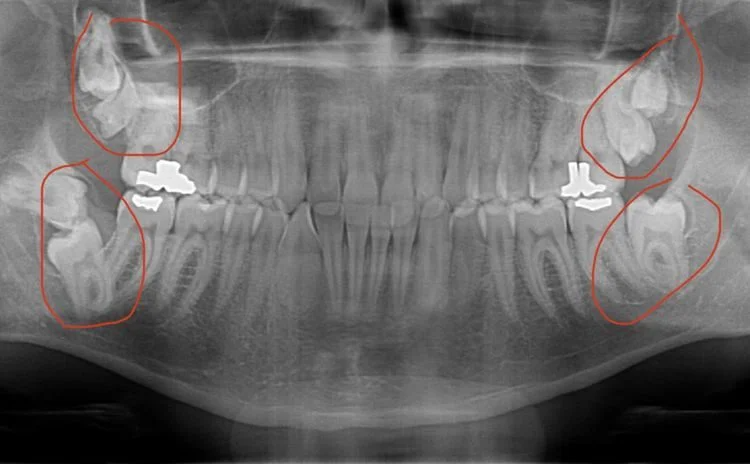

«У меня 7 зубов мудрости»